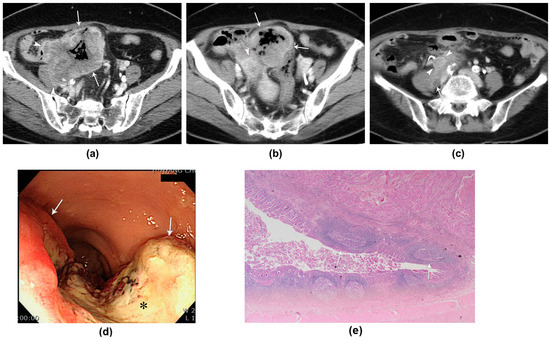

| 59/M | Hematochezia | CT, PET-CT | Rb | Circumferential wall thickening | 24 | Homogeneous | Moderate (1.22) | No | 10/21 | Yes | Levator ani muscle, prostate, urinary bladder | No |

| 86/M | Hematochezia | CT | Rb | Circumferential wall thickening | 25 | Homogeneous | Well (2.36) | No | 1/25 | Yes | Levator ani muscle | No |

| 54/F | Hematochezia | CT | Rb | Circumferential wall thickening | 19 | Homogeneous | Moderate (1.16) | Yes | 1/12 | Yes | No | No |